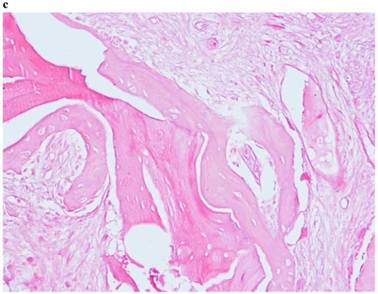

2) “Intermediate” protocol

The histological study of the samples collected from the “test-side” after 120 days shows a very encouraging histology, confirming the osteoconductive capacity of PRF used as osteoregenerative material. Histology proved that “the fragments are constituted by lamellar bone tissue with inhabited osteocyte lacunae, delimited by osteoblasts. The interposed stroma is relaxed and richly vascularized by capillary vessels. No inflammatory cell is revealed.” (Fig. 2)

Fig 2

Histological picture referring to “INTERMEDIATE Protocol”.